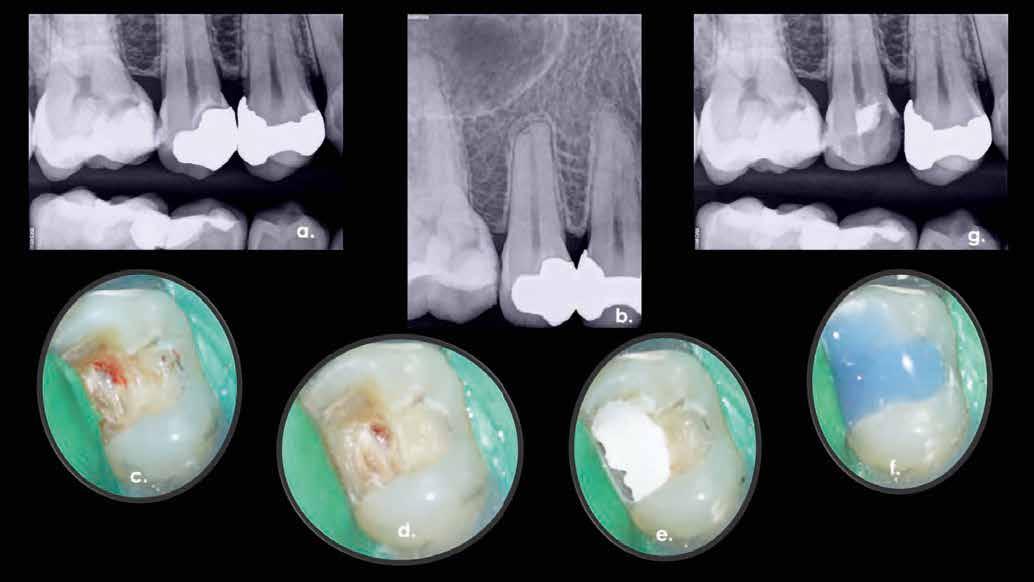

1. ábra: A 15-ös foggyökér meziális felszíne mellett látható radiolucens elváltozás, illetve a felvételen látható a korábban behelyezett gyökértömés, a parapulpális csap segítségével elhorgonyzott csonkfelépítés és a fogat borító cirkonkorona. –2. ábra: A saggitalis irányú CBCT-metszeten jól megfigyelhető az állcsontgerincet elérő radiolucens elváltozás. – 3. ábra: Az axiális irányú CBCT-metszeten egyértelműen látható a kezeletlen palatinális gyökércsatorna, valamint a radiolucens elváltozás mezio-disztális kiterjedése is jól megítélhető. – 4. ábra: A palatinális gyökércsatorna szelektív endodonciai kezelése során először gyógyszeres zárás került behelyezésre. – 5. ábra: A gyógyszeres zárás során alkalmazott kalcium-hidroxid alapú paszta a szulkuszon keresztül a szájüregbe extrudálódott. – 6. ábra: A gyökértömő anyag a középső és apikális gyökéri harmad határán lévő laterális csatornán keresztül a periapikális térbe extrudálódott. 7. ábra: A kezelések befejezését követően 4 évvel készült röntgenfelvételen jól látható a csontállomány gyógyulása és a fiziológiás gyökérhártyarés újbóli kialakulása. –8. ábra: A peroperatív CBCT-felvétel alapján készített koronális irányú metszeten jól látható a gyökércsúcs körül lévő periapikális felritkulás. – 9. ábra: A kezelések befejezése után 4 évvel készített CBCT-felvételen a gyulladásos lézió teljes megszűnése észlelhető.

10. ábra: A periapikális felvételen egyértelműen megmutatkozik a 46-os és 47-es fogak között kialakult csontos defektus, valamint a gyökereket fedő parodontális rostok károsodása. – 11. ábra: A disztális gyökér amputációját követően a csonthiány kiterjedése látszólag tovább növekedett. – 12. ábra: A 22 évvel később készített kontrollfelvételen jól megfigyelhető a csontos defektus telődése, valamint új kortikális csontállomány kialakulása.

A CBCT-készülékek endodonciai alkalmazásának talán az az egyik legnagyobb előnye, hogy így olyan anatómiai struktúrák is láthatóvá válnak, amelyeket egyébként nem tudnánk detektálni panoráma, cephalo, vagy periapicalis felvételek segítségével. Mivel a CBCT-felvételek kiértékelése számítógép segítségével történik, így a felvételek vizsgálata során lehetőségünk van az adott területet több nézőpontból és több síkban is megvizsgálni. 2015 októberében egy korábban a rendelőnkben kezelt 55 éves férfi páciens azzal a céllal kereste fel ismét a rendelőnket, hogy másodvéleményt kérjen egy jobb felső kvadránsban található fogával kapcsolatban. Egy másik rendelőben történő vizsgálat során a panaszos fog törését vélelmezték és a fog eltávolítását javasolták, illetve arról is beszámolt, hogy az elmúlt hét során ezen a területen egy puha duzzanat is kialakult. A klinikai vizsgálat során a jobb felső első és második kisőrlő között (14–15) egy fluktuáló duzzanatot észleltünk az áthajlásban. Az 15-ös fog mesialis oldalán 12 mm mély tasakot szondáztunk. A páciens által hozott periapicalis felvételen a 15-ös fog gyökércsúcsának mesialis részén egy nagy kiterjedésű radiolucens elváltozás volt észlelhető (1. ábra). A saggitális síkban vizsgált CBCT-felvételen (Carestream CS 9000, Carestream Dental) a lézió valódi kiterjedése is láthatóvá vált (2. ábra). A megelőző endodonciai kezelések során csupán a bukkális csatorna került detektálásra és gyökértöméssel való ellátásra. Az axiális irányú CBCT-szeleteken egyértelműen látható volt az ellátatlan palatinális gyökércsatorna (3. ábra)

Először kalcium-hidroxid alapú ideglenes gyógyszeres zárás került a palatinális csatornába (UltraCal XS, Ultradent Products; 4–5. ábra), amelyet 6 hét után a végleges gyökértömés elkészítése előtt eltávolítottunk. A gyökértömés elkészítése során meleg vertikális kondenzációs technikát alkalmaztunk. Radiológiai felvételen megfigyelhető volt, hogy a gyökértömő anyag egy laterális csatornán keresztül kis mennyiségben a periapicalis térbe extrudálódott (6. ábra). A 4 évvel később készített kontrollfelvételeken a lézió gyógyulása volt megfigyelhető (7–9. ábra). A vizsgálati eredmények és a kezelés kimenetele egyértelműen igazolta, hogy nem gyökérfraktúrával álltunk szemben, tehát a kezdeti diagnózis tévesnek bizonyult. Ez is azt erősíti, hogy korlátozott mennyiségben rendelkezésre álló adatok alapján nem lehet pontos diagnózist felállítani. Manapság szinte elengedhetetlen a CBCT-felvételek endodonciai beavatkozások során történő használata, feltéve, ha ezek elkészítése során az ALARA elv (as low as reasonably achievable) betartásra kerül.